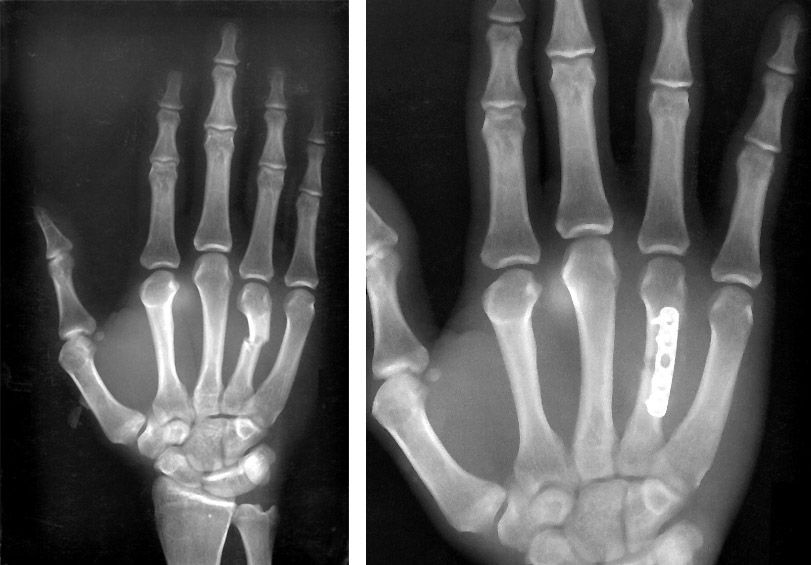

- डॉक्टर प्रभावित व्यक्ति के एक या एक से अधिक X-Ray करा सकते हैं ताकि फ्रैक्चर की जगह और गंभीरता का पता चल सके।

हाथ के फ्रैक्चर के कुछ मामलों में सर्जरी की आवश्यकता हो सकती है। खासतौर पर उस स्थिति में जब हड्डी के कई टुकड़े हो गए हों। इस दौरान कुछ वायर ,स्क्रू, पिंस, स्टेपल्स या प्लेट्स आदि का प्रयोग किया जाता है।

धातु की प्लेट्स और स्क्रूस: कुछ हाथ के फ्रैक्चर के मामलों में इनका प्रयोग किया जाता है। हड्डियों की सही एलाइनमेंट बनाये रखें के लिए इनका प्रयोग होता है।